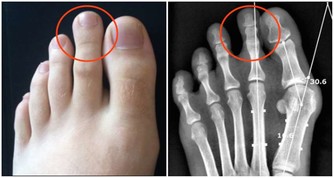

一、排除肝臟毒素檢查肝臟是否有毒的方法:1、指甲表面有凸起的稜線,或是向下凹陷。

中醫認為“肝主筋”,指甲是“筋”的一部分,所以毒素在肝臟蓄積時,指甲上會有明顯的信號。